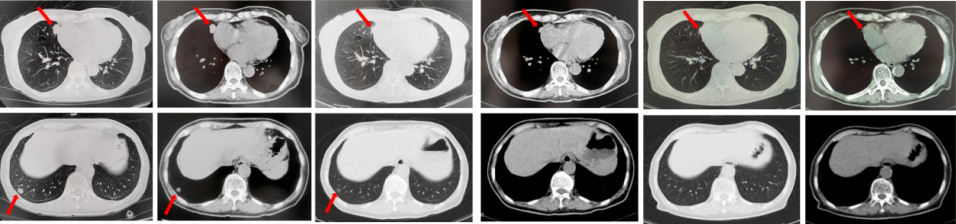

67岁女性患者,无既往病史。2019年10月患者因右侧季肋部不适行肺CT提示右肺中叶改变,双肺结节,右侧胸腔积液。行右侧胸腔穿刺引流,送检胸腔积液,液基薄层结果提示肺腺癌。确诊为右肺中叶恶性肿瘤cT2bN1M1a IVA期。基因检测(胸腔积液):EGFR L858R突变。建议患者口服奥希替尼,患者拒绝。2019年11月始口服埃克替尼,定期复查,最佳评效PR(图5)。

图5:A.第2例患者的基线影像资料,由上至下依次为右肺肿物、双肺转移灶及右侧胸腔积液;B.EGFR-TKI一线治疗后最佳复查评效,肺内病灶较前缩小,胸腔积液较前明显吸收。

2020年11月复查评效PD。复测基因检测(血检):T790M阳性,改行奥希替尼治疗,期间评效均为SD(图6)。

图6:A.埃克替尼靶向治疗后病情进展,肺内病灶较前增大,右肺近胸膜处新发转移灶;B.更换三代EGFR-TKI治疗后复查多处病灶未见明显变化。

如图7所示,2021年7月复查评效PD。重新行右肺穿刺取得病理,提示腺癌。NGS组织基因检测:MET基因扩增(变异倍数)4.0倍。改行赛沃替尼联合奥希替尼治疗。治疗10日后突发一过性寒战伴低血压,不除外药物相关,对症治疗后好转。复查评效达PR,因患者无法耐受药物不良反应,改行奥希替尼联合克唑替尼治疗至今,定期复查,最佳评效PR,末次评效SD(2024年7月)。

图7:A.奥希替尼治疗后病情进展,右肺内病灶较前再次增大,同时右肺内新发转移灶;B.出现MET扩增后,奥希替尼联合MET-TKI治疗后肺内病灶较前明显缩小;C.当前方案治疗持续有效。